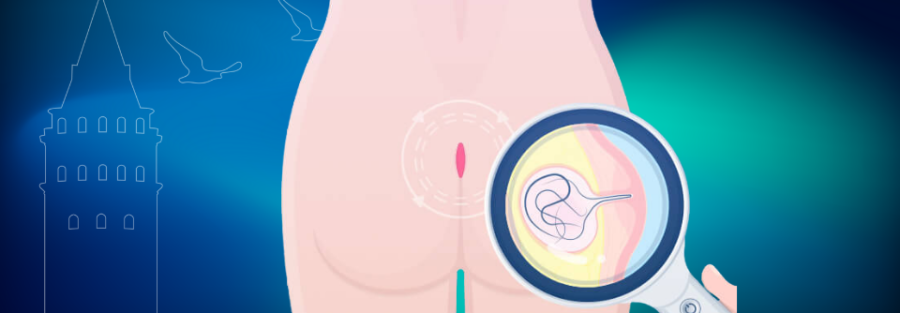

Kıl Dönmesi (Pilonidal Sinüs) Nedir? Belirtileri ve Tedavi Yöntemleri

Kıl dönmesi, vücuttan dökülen kılların genellikle kuyruk sokumu bölgesinde deri altına batmasıyla oluşan ve zamanla apse veya kistik yapıya dönüşebilen bir cilt enfeksiyonudur. İstanbul’da kıl dönmesi tedavisi konusunda uzman klinikler arasında Klinist modern ve etkili yöntemler sunmaktadır. Kıl dönmesi genellikle ağrı, şişlik ve kötü kokulu akıntı gibi semptomlarla kendini gösterir. Tedavi edilmezse kronik bir hal alabilir ve apselere yol açabilir.

Tıbbi adı pilonidal sinüs olan kıl dönmesi, dökülen tüylerin deri altına batması ya da kılların cilt içine doğru büyüyerek kistik bir yapı oluşturmasıyla meydana gelir. Erkeklerde hormon seviyelerinin 20’li yaşlardan itibaren artması, kıl büyümeyi tetikleyerek hastalığın gelişmesine zemin hazırlayabilir. Ayrıca hareketsiz yaşam tarzı, obezite, uzun süre oturma ve kalın vücut kıllarına sahip olmak da kıl dönmesine neden olan faktörler arasındadır.